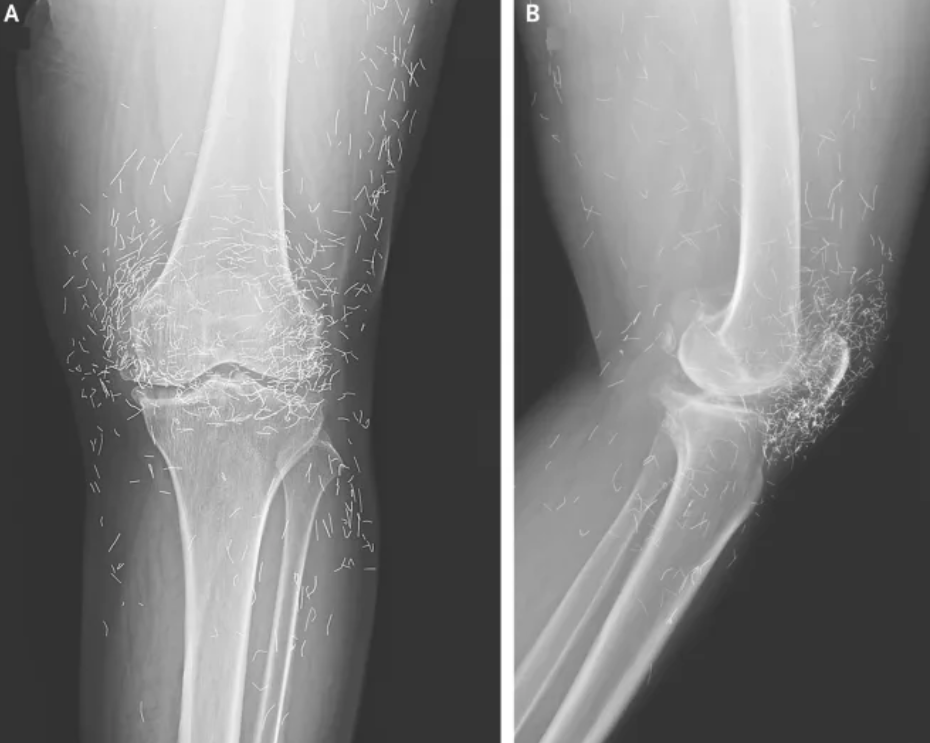

There are other complications as well. Needles lodged in tissue can interfere with medical imaging. “They can obscure parts of the anatomy on an X-ray,” Guermazi noted. Even more alarming, patients with metal fragments in their bodies should never undergo an MRI, as the magnetic force could cause the needles to move — potentially puncturing blood vessels and causing life-threatening damage.

A X-ray of the patient’s knee showing acupuncture needles embedded in the tissue, Photo Credit: Reddit

As for the South Korean woman, her case was recently documented in the New England Journal of Medicine. While the needles may have been intended to help, her X-rays tell a cautionary tale about the potential risks of extreme alternative therapies.